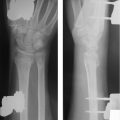

Medullary compression screws should be placed within the central 1/3rd of the scaphoid in both AP and lateral radio-graphs. This has been shown to have 43% stiffer construct and improved alignment and range of motion compared to eccentric placement. 8 Central placement has also been shown to have decreased time to union when compared with eccentric screw placement (► Fig. 41.3). 9

Cannulated screw technique has been found to have a higher rate of central placement when compared to an external reference guide. 9